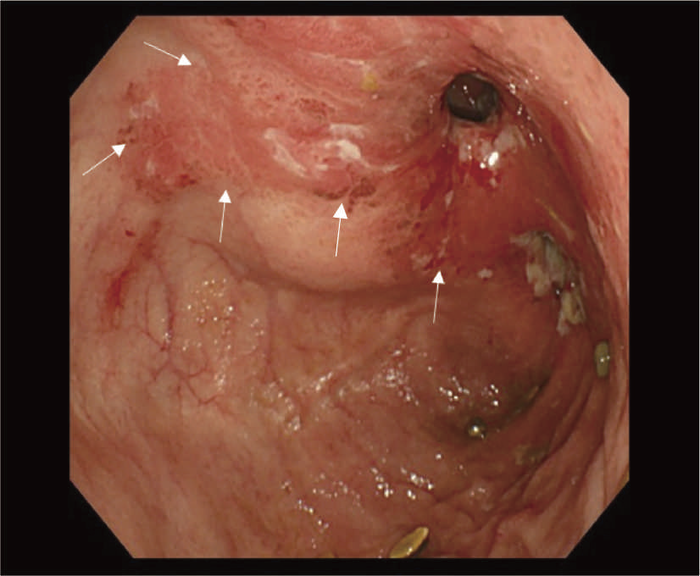

図5 UC関連粘膜下層浸潤癌の内視鏡所見

- 白色光像:直腸(直腸S状部)の発赤調変化。背景粘膜は寛解期にあった。

- 色素内視鏡像:病変辺縁が明瞭となるが,病変肛門側で不明瞭であった。

- NBI拡大像:口径不同,不均一な微小血管と不整な表面構造所見を認めた。

- pit pattern像:小型の類円形,管状pitを認めた。